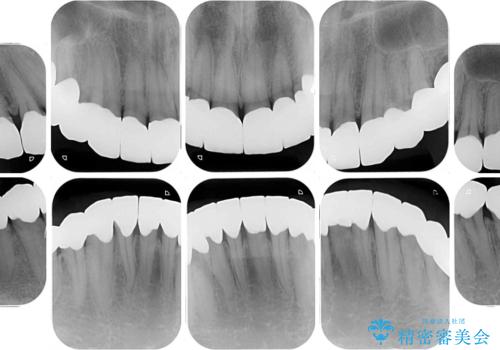

咬み合わせを改善するに当たって、抜歯しなければならない歯や歯列の改善が必要な箇所があったため、矯正治療やインプラント治療から始めていくこととしました。

不自然なくらい真っ白にしたいとのことでしたので、透明感のないフルジルコニアクラウンを用いて補綴することとしました。

本来、あまりにも不自然な歯となるため、フルジルコニアクラウンを前歯に使用することは、咬合力が強すぎる場合を除き、ほとんどありません。

それでも、色調、形態ともに不自然なくらい真っ白な歯をご希望でしたので、患者様には大変満足していただきました。